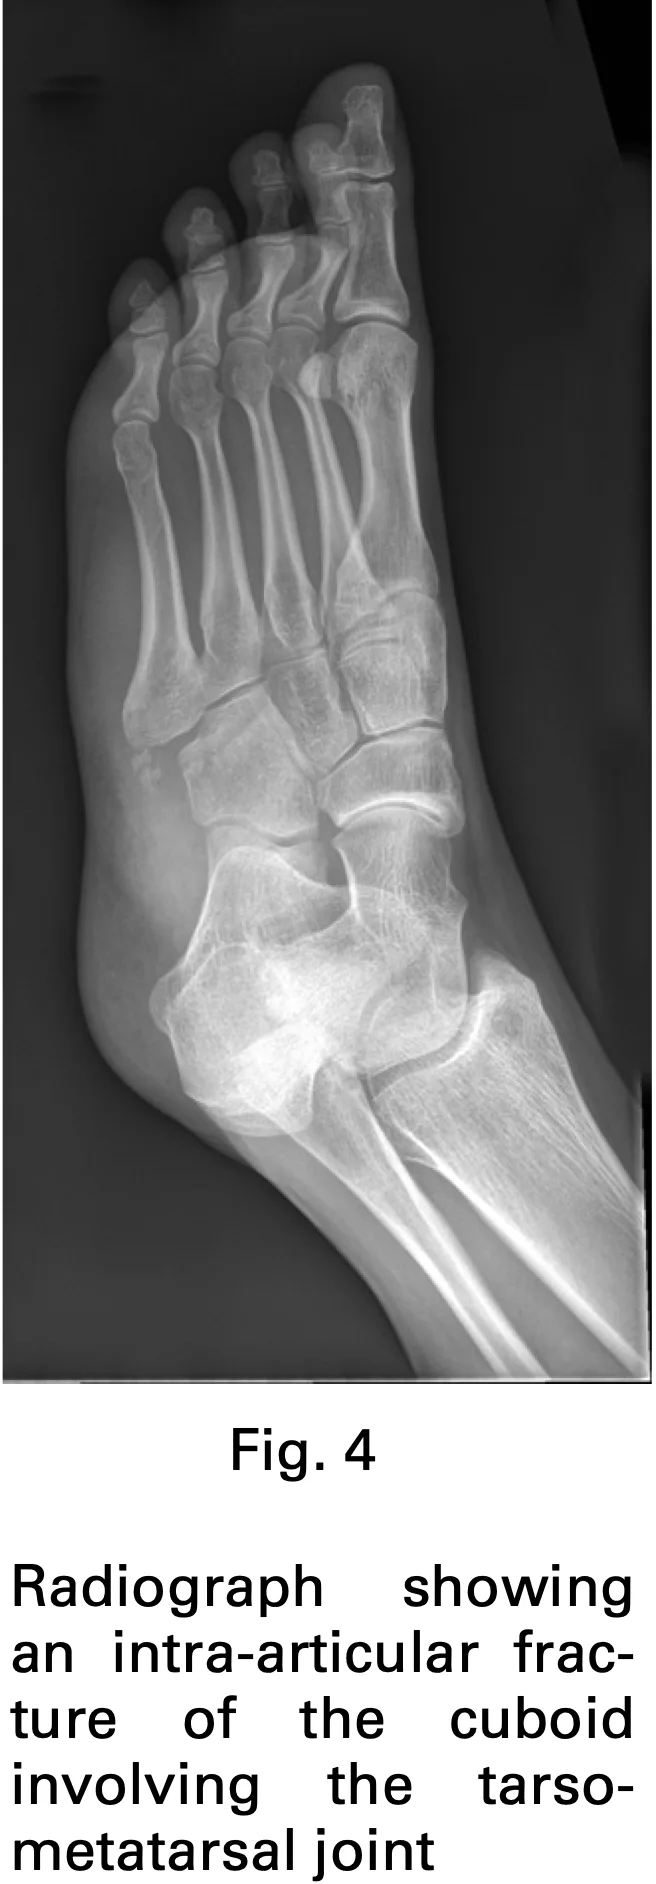

外果・立方骨骨折の患者

2人目は, 前日に屋外で転倒して以降, 足の痛みが続いている中高年の方.

歩行困難で、車イスでの受診でした.

足背に腫脹と圧痛を認め, 中足骨・足根骨骨折を疑ってCTを撮像.

結果は, 外果(外くるぶし)と立方骨の骨折.

いずれも転位は軽度であったため, 保存療法を選択しました.

ギプス副子で固定し, 松葉杖を貸与.

免荷を指示し, 来週のギプス固定の予約を入れて終了としました.